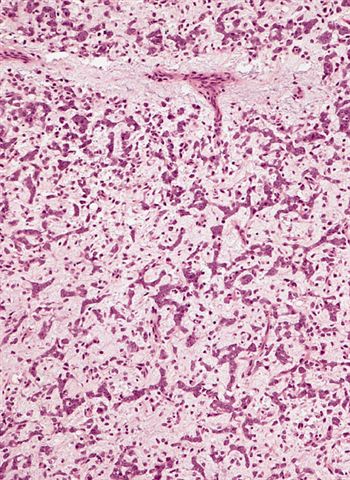

The microscopic image above depicts the histologic appearance of a soft tissue mass resected from the thigh of a 37 year old man and is representative of the entire lesion. Which of the following is true regarding the diagnosis?

D. Majority of cases harbor t(12;16) FUS::DDIT3 gene fusion. The microscopic image depicts a low grade myxoid liposarcoma characterized by a proliferation of bland stellate tumor cells embedded in a myxoid matrix with a prominent plexiform capillary network and scattered signet ring lipoblasts. There is no mitotic activity or pleomorphism. The majority of cases of myxoid liposarcoma harbor a t(12;16) FUS::DDIT3 gene fusion. Answers B and C are incorrect because the t(9;22) EWSR1::NR4A3 gene fusion is characteristic of extraskeletal myxoid chondrosarcoma and the t(7;16) FUS::CREB3L2 gene fusion is characteristic of low grade fibromyxoid sarcoma. Answer E is incorrect because classification of myxoid liposarcoma as high grade requires > 5% of the sampled lesion to consist of a hypercellular round cell component according to the WHO. Cases with borderline round cell component (< 5%) are regarded as having areas of transition, a designation of unclear diagnostic significance. Answer A is incorrect because immunohistochemistry for MDM2 is negative in myxoid liposarcomas.